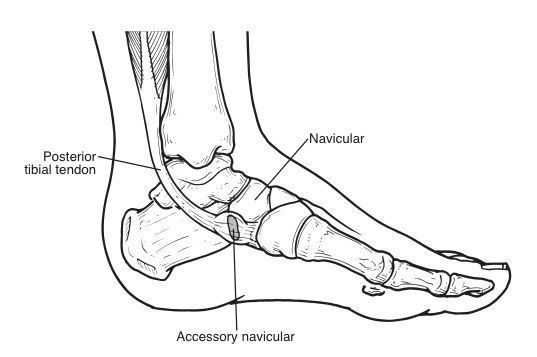

As well as treating adult knee conditions, both @mrnevdavies & @rdadodds have a specialist interest in Children’s Orthopaedics & Trauma. Accessory Navicular Bone is one of the conditions we treat. There is lots of helpful information on our website. buff.ly/2NRpOvN #RHKU